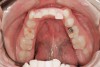

Figure 22  Incisal view demonstrates the damage from sleep bruxism and the erosive wear associated with GERD and tongue position.

Figure 22

The majority of patients in the mature group will have at least mild apnea. Medical issues related to overall health may be linked to OSA. Bruxism may be present but will be limited in its ability to clear the airway and reduce GERD. Patients may need to address tooth wear issues that have been compounded through years of neglect (Figure 21 and Figure 22). Comprehensive evaluation for signs and symptoms of OSA and referral for polysomnographic study is recommended. Patients with dentures should be encouraged to wear their dentures at night if sleep disruption is present (Figure 23 and Figure 24).